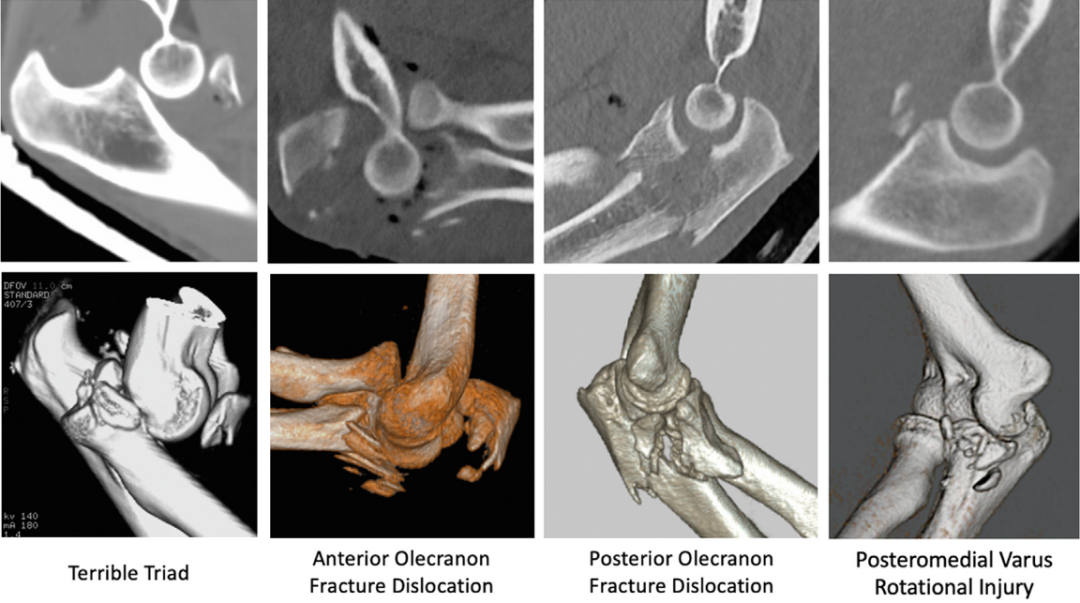

几乎所有冠突骨折病例均建议行二维及三维重建CT检查,该检查可清晰评估肱尺关节的对合情况,更精准地显示骨折的形态、粉碎程度,明确损伤模式,同时为手术方案的制定提供影像学依据。

冠突骨折极少单独发生,多为复杂肘关节不稳定损伤的组成部分。基于O’Driscoll分型对冠突骨折形态的描述,结合损伤机制及合并损伤的差异,可将其分为三种主要损伤模式:合并冠突尖部骨折的后外侧旋转不稳定、合并前内侧关节面骨折的后内侧旋转不稳定、合并基底骨折的轴向负荷损伤。

亚型1为冠突尖小骨片骨折(<2mm),多合并单纯肘关节脱位;亚型2为骨折块更大的尖部骨折(>2mm),骨折块通常不超过冠状突高度的1/3,典型见于肘关节 “恐怖三联征”,由前臂旋后状态下的轴向负荷联合外翻应力导致的后外侧旋转不稳定引起,常合并桡骨头骨折和外侧副韧带复合体撕裂,内侧副韧带可受累,但并非所有病例均出现损伤。

典型合并内翻后内侧旋转不稳定,该损伤由前臂旋前状态下的轴向负荷联合内翻应力导致,肘关节半脱位使肱骨滑车内侧与冠状突前内侧关节面发生撞击,进而引发骨折。常合并内侧副韧带后束及外侧副韧带复合体撕裂,桡骨头可受累,但内侧副韧带前束通常保持完整。

由肘关节轴向负荷导致,肱骨远端向尺骨半月切迹撞击,引发冠突骨折,部分病例可合并尺骨近端骨折,形成经尺骨基底冠状突骨折-脱位。该类型骨折常合并桡骨头骨折,韧带损伤可继发旋后肌嵴或尺骨干骺端内侧的撕脱骨折。